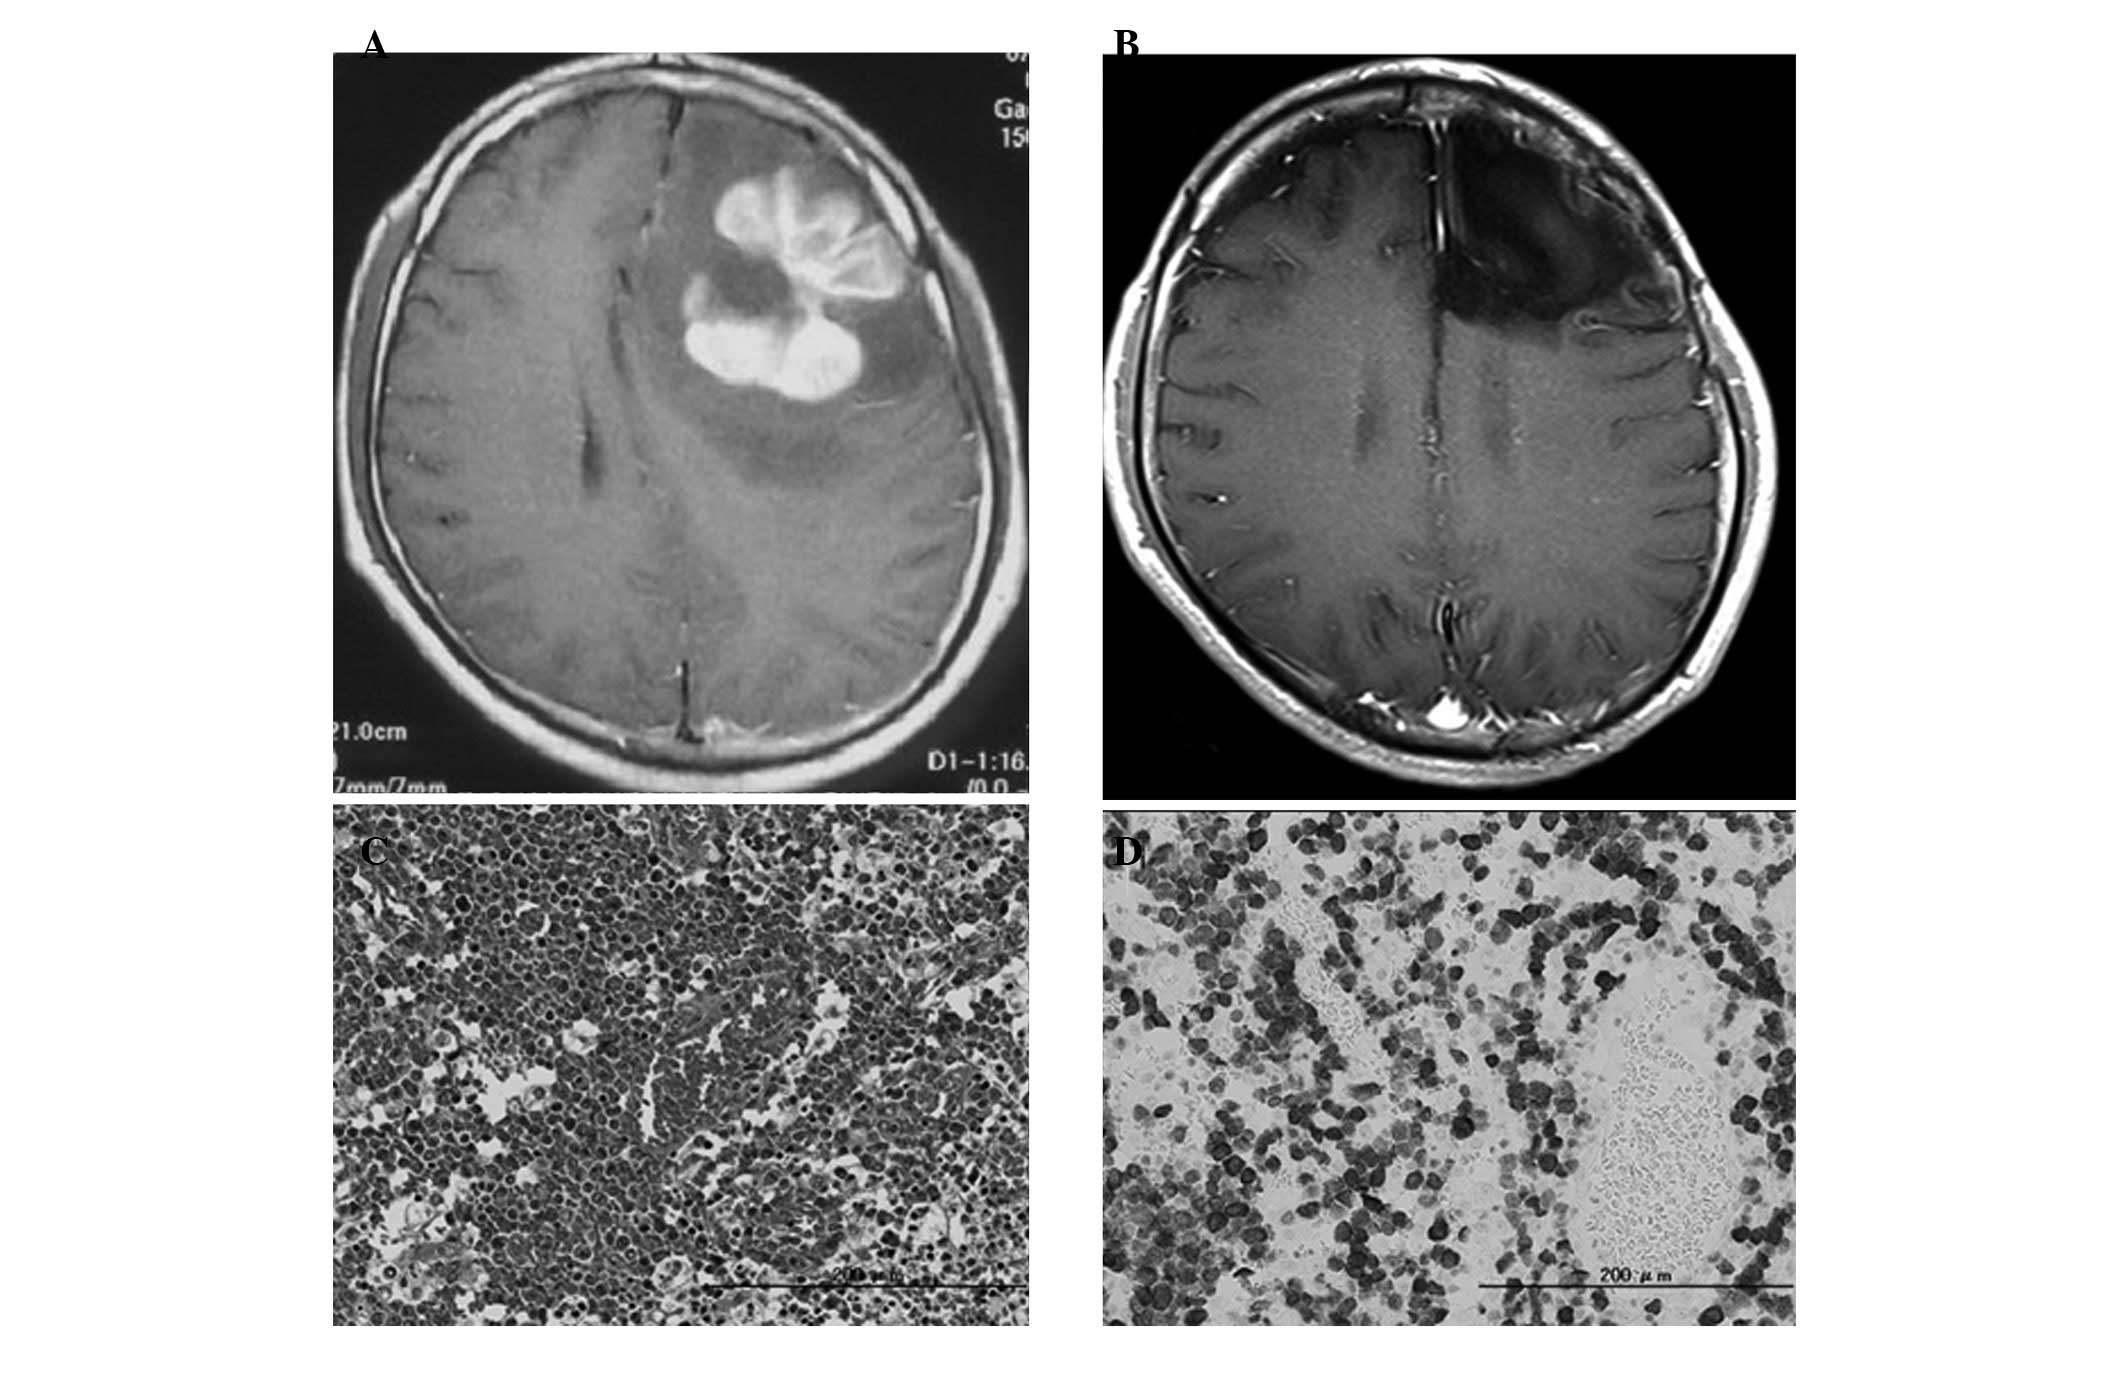

We have treated 90 cases of histologically proven PCNSL from 2000 to the present at our department, including 88 cases of DLBCL and 2 cases of T-cell lymphoma, including 1 ALCL. A 20-year-old immunocompetent man with no other significant medical history was hospitalized with generalized seizures. He did not have any neurological deficits and physical examination on admission revealed no abnormal findings. Complete blood counts and serum chemistries, including LDH and soluble interleukin-2 receptor levels, were normal. Magnetic resonance imaging (MRI) with gadolinium diethylenetriamine pentaacetic acid (Gd-DTPA) revealed a well-enhanced mass lesion in the left frontal lobe (Fig. 2A), with a surrounding high-intensity lesion on T2-weighted images, indicating significant edema. Whole-body CT scans with contrast medium revealed no abnormality. Based on the suspicion of high-grade glioma, awake brain surgery and gross total removal of the tumor were performed. No residual tumor was identified on postoperative MRI with Gd-DTPA. Pathological findings revealed the proliferation of large, atypical lymphocytes containing scattered horseshoe-shaped nuclei on hematoxylin and eosin (H&E)-stained slides (Fig. 2C). Immunohistochemistry revealed that the tumor cells were positive for CD3 and ALK-1 (Fig. 2D), but negative for CD20. This patient was finally diagnosed with ALK-1-positive ALCL. Bone marrow examination findings were normal.

Figure 2

Preoperative magnetic resonance imaging (MRI) with (A) gadolinium diethylenetriamine pentaacetic acid (Gd-DTPA), (B) MRI 5 years after treatment, (C) hematoxylin and eosin (H&E) staining and (D) immunohistochemistry for anaplastic lymphoma kinase 1 (ALK-1).

Treatment was immediately initiated with intravenous HD-MTX (3.5 g/m2). The patient completed 3 courses of HD-MTX, one every 2 weeks. Cerebral MRI and systemic positron emission tomography with fluorodeoxyglucose (FDG-PET) revealed no abnormal findings and radiotherapy was not performed. He had regular MRI examinations every 3 months until 3 years after the diagnosis and every 6 months thereafter. There has been no recurrence of the disease for 5 years (Fig. 2B) and the patient has exhibited no neurological deficits.